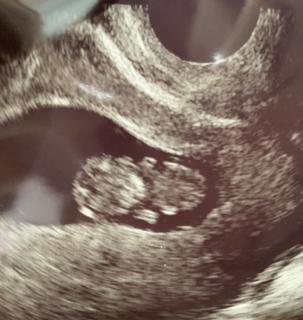

写真:9w4d:ゆーちゃんさん

9w4dのエコー写真です。 前回5w5dのときは分かりませんでしたが、 今回の双子だということが判明しました。 嬉しい反面、不安な気持ちもありますが、お腹の子たちがすくすく育ってくれたらと祈るばかりです。

9w4dで大きさは2.21cmです。頭と身体が別れ、二頭身になっていて感動しました。まだ手足や、その他の人間らしい形は見えません。前回は初めての受診で7w2d、袋のなかに豆が一つあるようなエコーでした。

9週4dのエコー写真です。23mmです。 動きもあって、大きさも標準とのこと。前回は小さくて予定日決定できなかったのですが、今回はバッチリでした。検診後、その足で母子手帳もらいに出掛けました。つわりがひどくふせっていたので母子手帳をもらえてすごく嬉しく思いました。